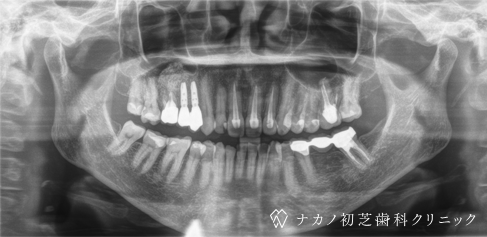

インプラント・7本 (70代男性)

-

BEFORE

AFTER

年齢 70代男性

治療内容 インプラント治療7本(骨造成の併用)

インプラント治療とは、歯を抜いた所にチタン製の人工歯根を埋入し、その上に歯を入れる方法です。骨を増やすことで、より審美的に治療が出来ました。費用 1本 400,000円(税込 440,000円)

リスク・副作用

腫れ・疼痛・違和感を感じるなどの症状を生じることがあります。